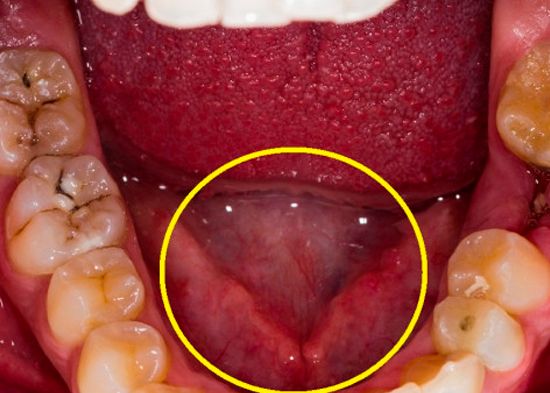

El Torus o rodete mandibular, se trata de un crecimiento anormal del hueso tori en el maxilar inferior, debajo o a los lados de la lengua, creando la aparición de pequeños nódulos óseos. Aunque no causan dolor, suelen ser antiestéticos y pueden confundirse con tumores malignos.

De acuerdo con un estudio publicado por la Canadian Medical Association Journal, el torus mandibular puede ser bilateral y de lento crecimiento, sin embargo, cuando el hueso es suficientemente grande como para tocarse en la línea media de la boca, ocasiona dolor o alteraciones en las funciones de los dientes.

Hagamos un pequeño experimento, desliza tu lengua alrededor de las encías inferiores y tu paladar, ¿sientes un ligero bulto extraño? Si es así, lo más probable es que se trate de crecimiento de toris cubierto por la encía, también pueden causar úlceras en los tejidos blandos, inflamación de la encía, dolor en la mandíbula, dientes flojos, habla arrastrada.